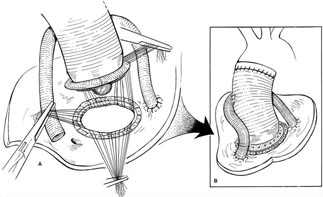

Bentall prosedürü ile asendan aort anevrizması tamiri (yapay aort kapağı ve yapay damar kullanılarak)

Cabrol prosedürü ile asendan aort anevrizması tamiri (yapay aort kapağı ve yapay damar kullanılarak)